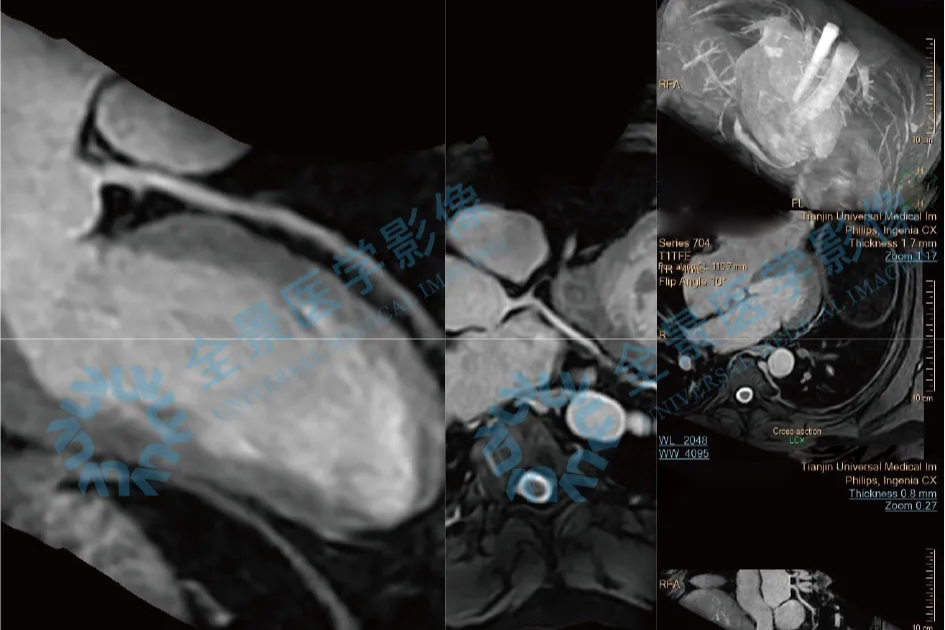

碘过敏无法做冠脉 CTA,心脏核磁解除心梗担忧

2025-12-19